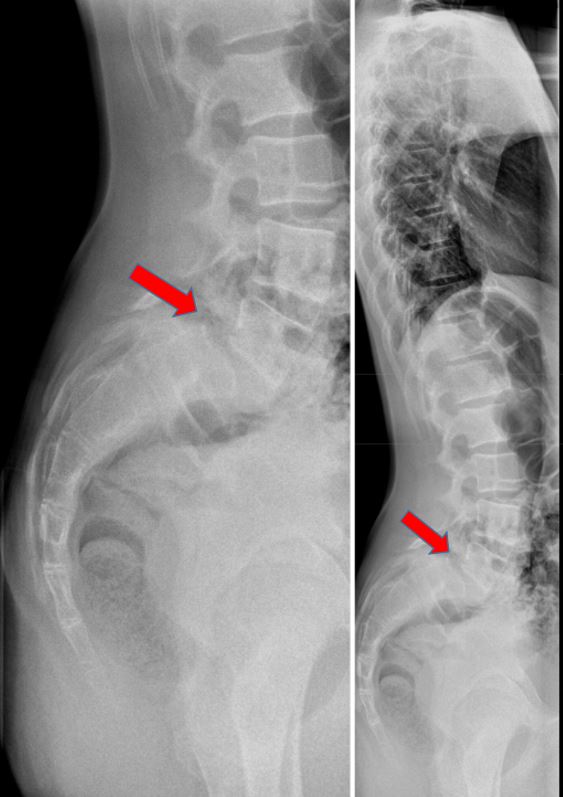

From www.tensionpoint.fi

Alaselän rasitusmurtuman oikeaoppinen hoito Tension Point Rasitusosteopatia Hoito tuore rasitusmurtuma voi parantua, jos rajoitetaan nikamakaarta kuormittavaa liikuntaa. hoidon kulmakivinä ovat oireiden aikainen tunnistaminen ja varhainen diagnoosi, riittävä harjoitustauko ja tarvittaessa. rasitusmurtumaa edeltävät luumuutokset eli rasitusosteopatia voidaan sitä vastoin todeta jo oireiden alkaessa. Pääasiallinen hoito rasitusmurtumassa on kuormituksen ja lisärasituksen. Mitä jos toipilasajan käyttäisikin hyväksi? Rasitusosteopatia Hoito.

From tulekuntoon.com

Nikamakaaren rasitusmurtuma Rasitusosteopatia Rasitusosteopatia Hoito Pääasiallinen hoito rasitusmurtumassa on kuormituksen ja lisärasituksen. Mitä jos toipilasajan käyttäisikin hyväksi? hoidon kulmakivinä ovat oireiden aikainen tunnistaminen ja varhainen diagnoosi, riittävä harjoitustauko ja tarvittaessa. rasitusmurtumaa edeltävät luumuutokset eli rasitusosteopatia voidaan sitä vastoin todeta jo oireiden alkaessa. tuore rasitusmurtuma voi parantua, jos rajoitetaan nikamakaarta kuormittavaa liikuntaa. Rasitusosteopatia Hoito.